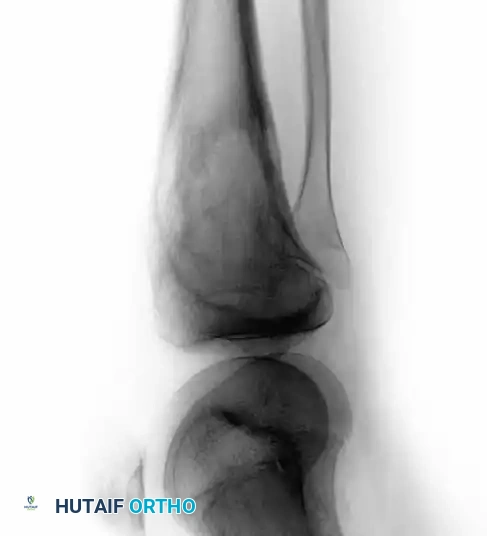

Intraoperative Imaging and Margin Assessment

Continuous intraoperative assessment using fluoroscopy and frozen section pathology is mandatory. The following images demonstrate various stages of complex upper extremity resections, allograft preparations, and prosthetic implantations across the humerus and elbow joint.

Distal Humerus and Elbow Reconstruction

When tumors involve the distal humerus, resection often requires sacrifice of the collateral ligaments and the articular surface of the elbow. Reconstruction is typically achieved using a linked, semi-constrained total elbow arthroplasty designed for oncologic defects.